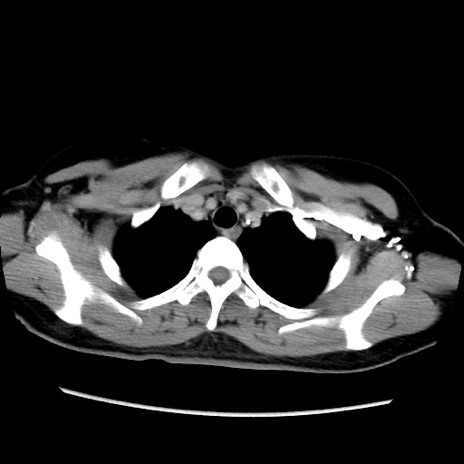

症例39(横断像)

【症例】40歳代女性

【主訴】上下腹部痛

【現病歴】2日目から下腹部痛あり。夜間は痛みで眠れなかった。昨日より上腹部痛と下痢が出現。臥位で痛みは軽快したため、休んでいた。本日になって臥位でも立位でも痛みが強くなってきたため救急要請。

【既往歴】子宮内膜症

【身体所見】部:平坦・軟、左上下腹部に圧痛あり、反跳痛あり。

【データ】WBC 21800、CRP 26.78